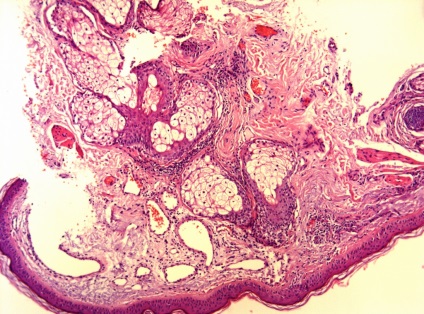

Ma már többféle bőr biopszia, köztük - tűbiopszia, excisional biopszia és derma biopszia. Dermatomális és excíziós bőr-biopszia végre az „akut” vagy „nyitott” módon. Amikor egy szikével biopszia dermatomális felületi réteg a bőr, míg a excisional biopszia - kivágtuk nagyobb bőrterületet, majd varrókészülék (fénykép 1). Ugyanezt a technikát használunk, és ha a biopszia musculocutaneous csapóajtót, ha egyidejűleg kimetszett bőr, a bőr alatti szövet és izom lebeny alá.

Ábra. 5 érelváltozások a bőr - egy jelzés a biopszia dermatomá

Ábra. 6,7,8 érelváltozások a bőr - jelzi biopszia a bőr graft

Következtetés (patológus MD Karev VE): egy jóindulatú daganat tömegének faggyúmirigy; haemangiomatosis bőrben, cutan vasculitis (gyulladásos elváltozások érfalak).